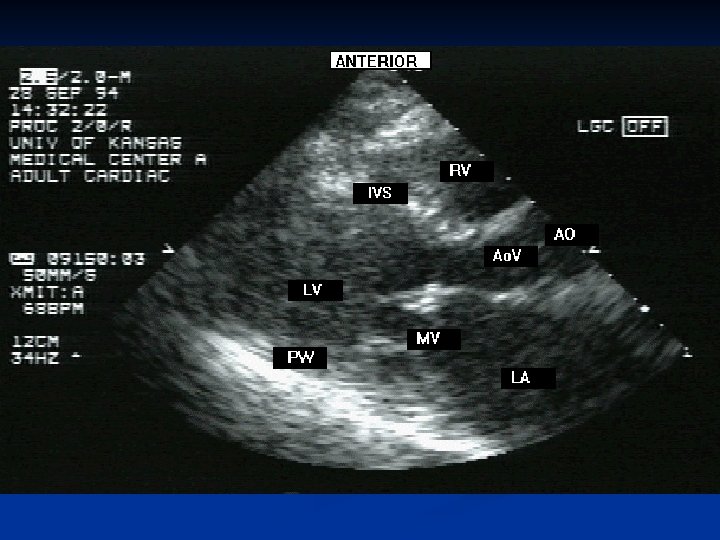

n ECHO CARDIOGRAM—THICKENED , IMMOBILE CUSPS, REDUCED RATE OF DIASTOLIC FILLING. REDUCED VALVE AREA. CARDIAC CATHETERISATION— PRESSURE GRADIENT BETWEEN LA AND LV n

Mitral Stenosis